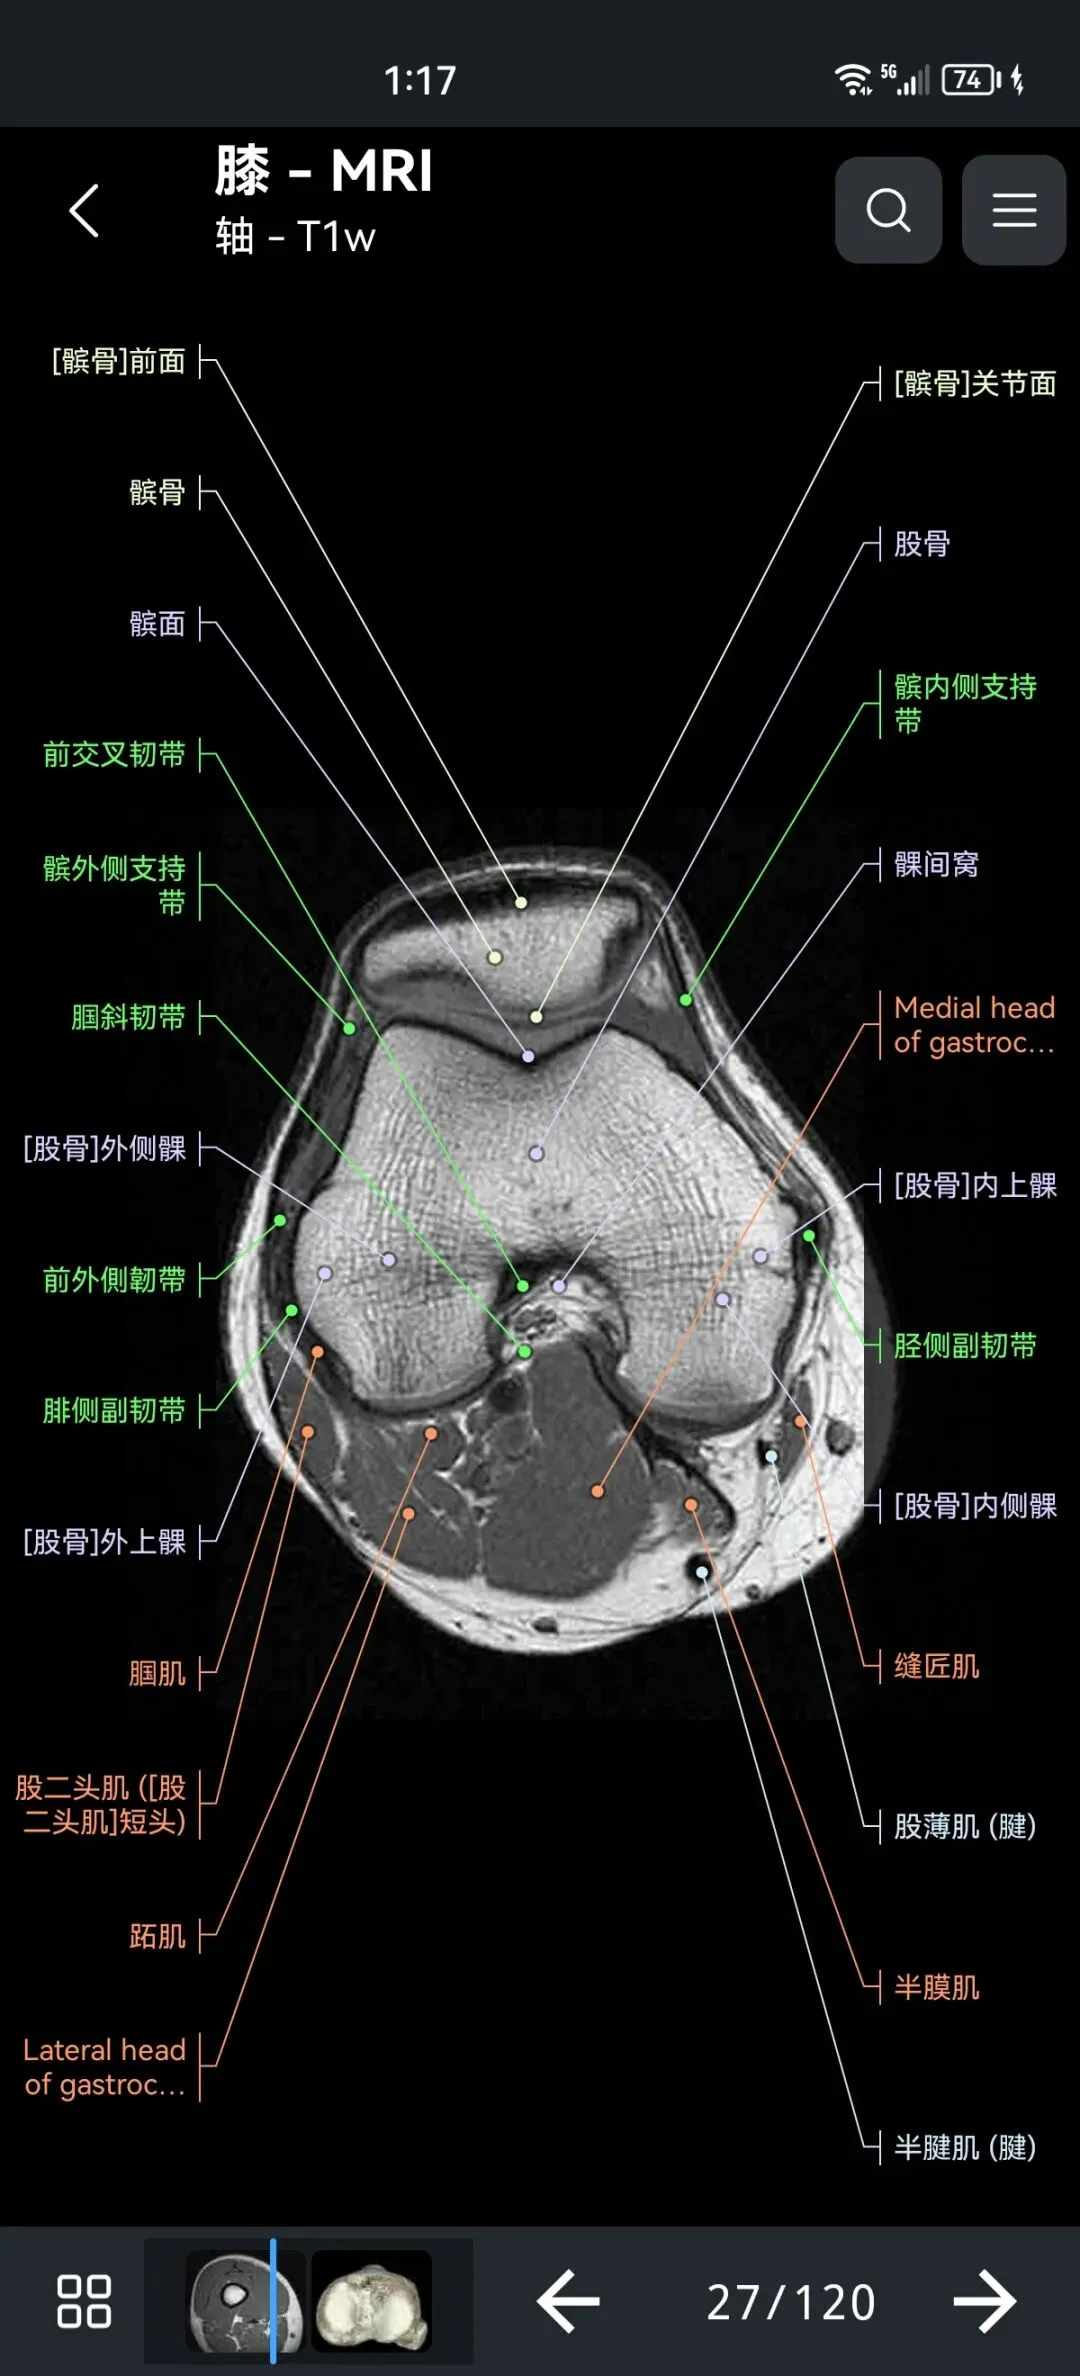

🌈这是国外引进的一款专业影像解剖学习软件。

覆盖了X光、CT、MRI、断层大体解剖、核医学、介入造影、医学插图等多个模块,覆盖全身各个系统的影像解剖(正常解剖结构,无病例),其中的解剖结构高达87万个,结构标注超精细,超高清图像,历时两年研发设计完成✅。